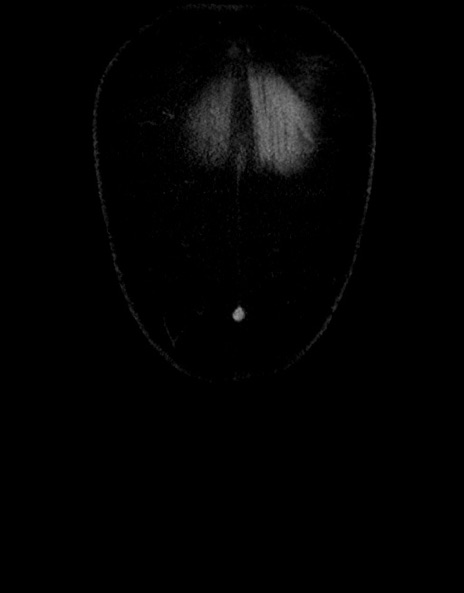

症例